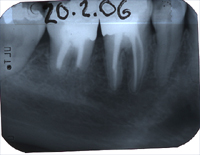

Wieder ein Jahr später machen wir ein Routineröntgenbild der beiden wurzelbehandelten Zähne und stelle beim hinteren Zahn einen beinahe haselnussgrossen Herd fest (Abb. 6). Der Zahn ist zwar schmerzfrei, aber sicher nicht entzündungs- und keimfrei; möglicherweise ist es sogar eine Zyste?

Die Situation konnte so nicht belassen werden. Es gab zwei Möglichkeiten:

Jetzt erst konnte der operative Eingriff zur Erhaltung des zweithintersten Zahnes geplant werden. Abb. 7 zeigt das Röntgenbild direkt nach dem operativen Eingriff mit den entfernten Wurzelspitzen (schwarzes Loch auf dem Röntgenbild). In Abb. 8 erkennt man 23 Jahre später die beiden wurzelbehandelten Zähne mit absolut gesunden Knochenverhältnissen und schmerzfrei. Es war an diesen Zähnen kein einziger weiterer Eingriff in all den Jahren mehr nötig gewesen.

Warum aber war trotz perfekter Wurzelfüllung am hinteren Zahn noch ein operativer Eingriff nötig? Die Ursache liegt in der Anatomie des Zahnes. Es kommt nicht selten vor, dass neben dem Hauptwurzelkanal sogenannte Seitenkanäle vorhanden sind, die so klein sind, dass sie röntgenologisch nicht sichtbar werden. Diese Seitenkanäle, wie sie schematisch in Abb. 9 links zu sehen sind, gewinnen dann an Bedeutung, wenn der Zahn, wie in diesem Fall, seit längerer Zeit abgestorben ist (erbsengrosses Granulom zu Beginn der Behandlung).